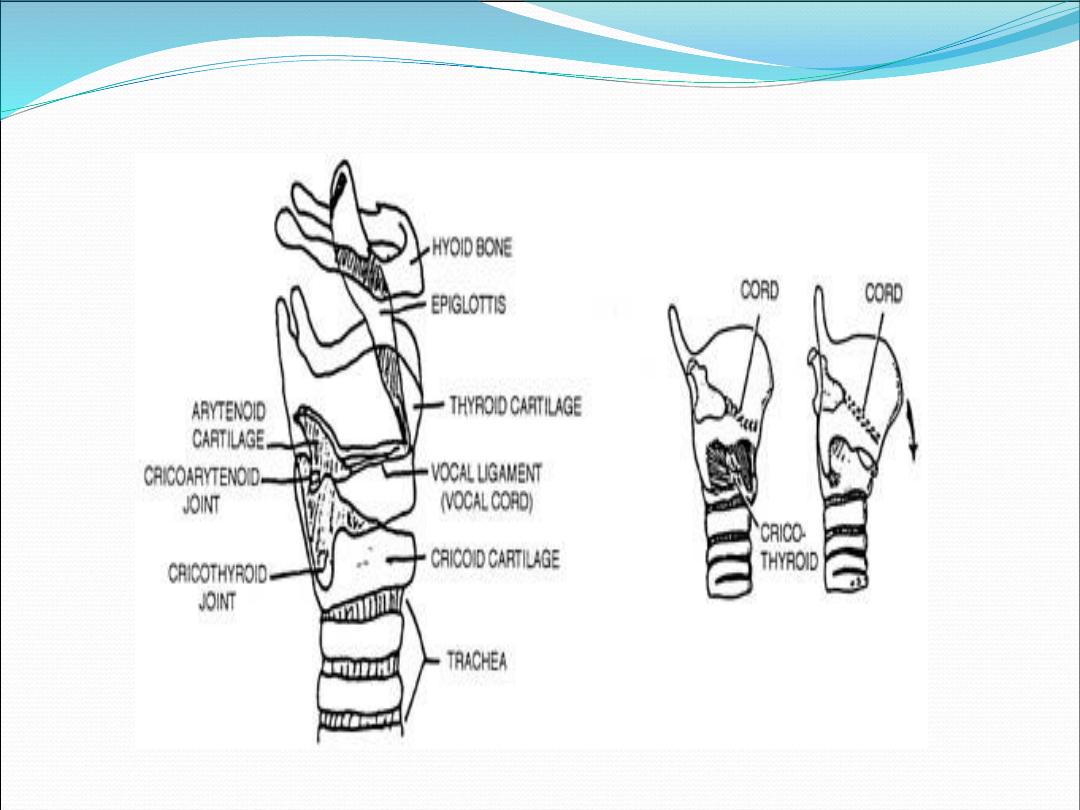

Cartilages of the larynx

1.

Thyroid cartilage (single)

2.

Cricoid cartilage (single)

3.

Epiglottis (single)

4.

Arytenoid cartilages (paired)

5.

Corniculate cartilages (paired)

6.

Cuneiform cartilage (paired

)

It is commonly described as part of the

laryngeal framework, because it is an

important point of attachment for

extrinsic muscle of the larynx

1.

Thyrohyoid membrane

2.

Cricothyroid membrane

3.

Cricotracheal ligament

4.

Vocal ligament